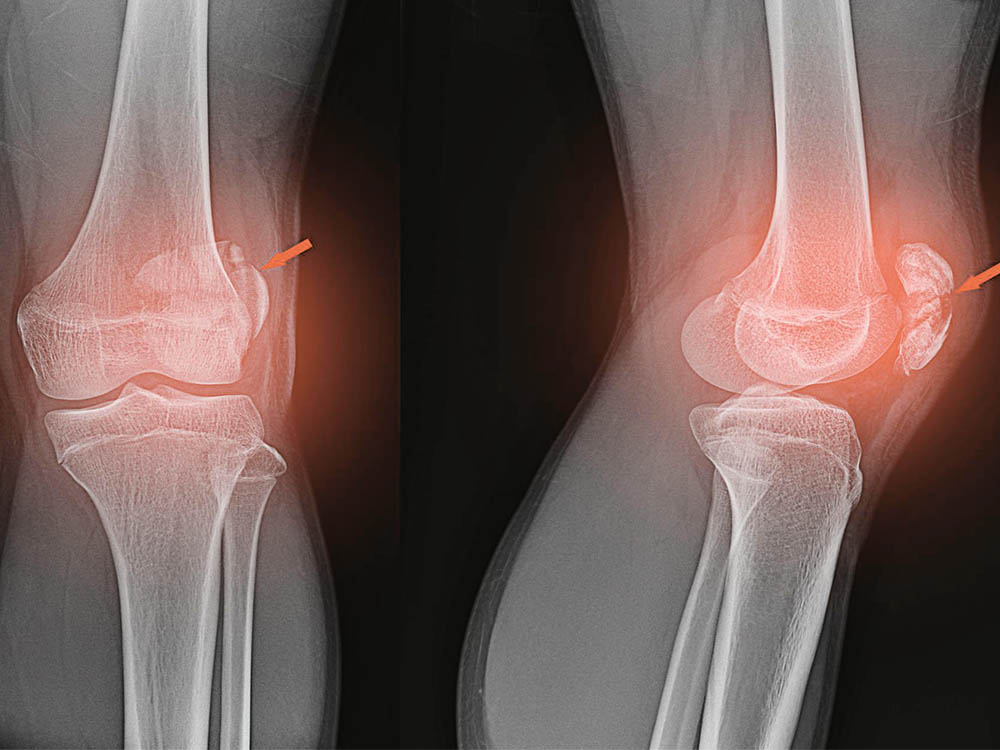

Рекурвация коленного сустава: рентгеновские снимки и объяснения